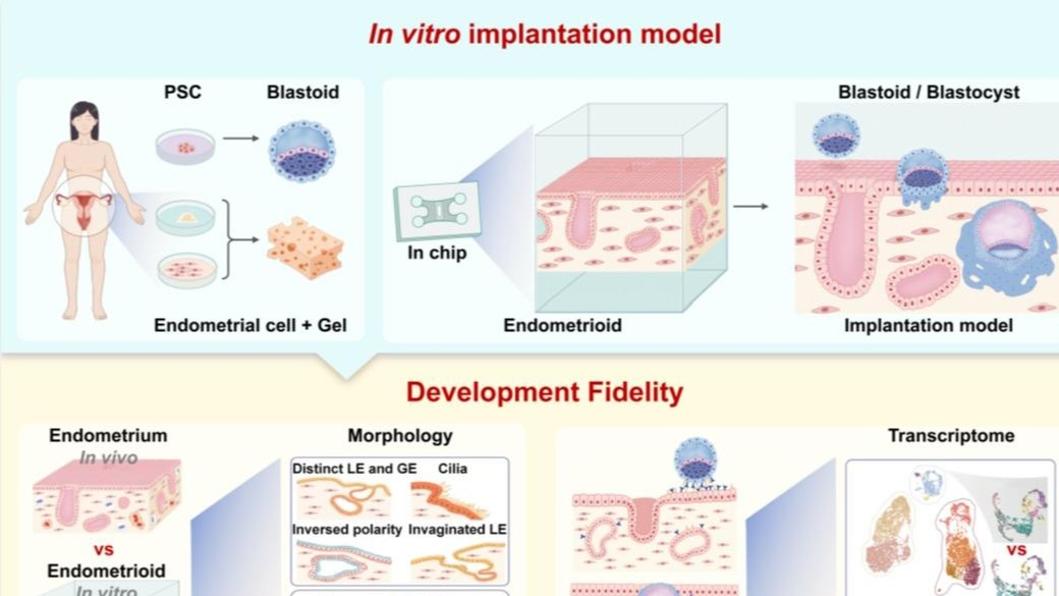

科研新突破!这项技术有望探明胚胎移植失败原因

记者从中国科学院动物研究所获悉,该所于乐谦、王红梅研究员联合国内外科研团队,成功研发出基于微流控芯片的3D胚胎植入模型(3D子宫模拟芯片),首次在实验室完整复刻人类胚胎着床过程。相关成果12月23日在国际学2025-12-24 -